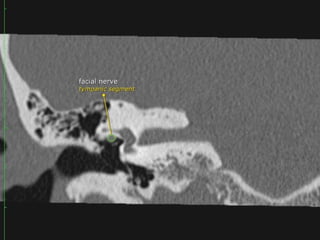

Segments

 tympanic segment (from geniculate ganglion to pyramidal eminence): 8-11 mm

long, zero branches

Anterior tympanic level TheTM may be identified as a thin filamentous structure extending from the scutum superiorly and coursing parallel to the plane of the long process of the malleus to attach to the limbus inferiorly. The head and neck of the malleus can be seen in the epitympanic space, with the tendon of the tensor tympani muscle attaching to neck. The labyrinthine and tympanic segments of the facial nerve are seen as two lucencies superior to the cochlea. Midtympanic level This level shows the long process and lenticular process of the incus and the incudostapedial articulation as an L- shaped configuration. Prussak’s space is seen between the incus and scutum. The tympanic segment of the facial nerve canal is seen along the medial wall of the middle ear just superior and lateral to the cochlea.